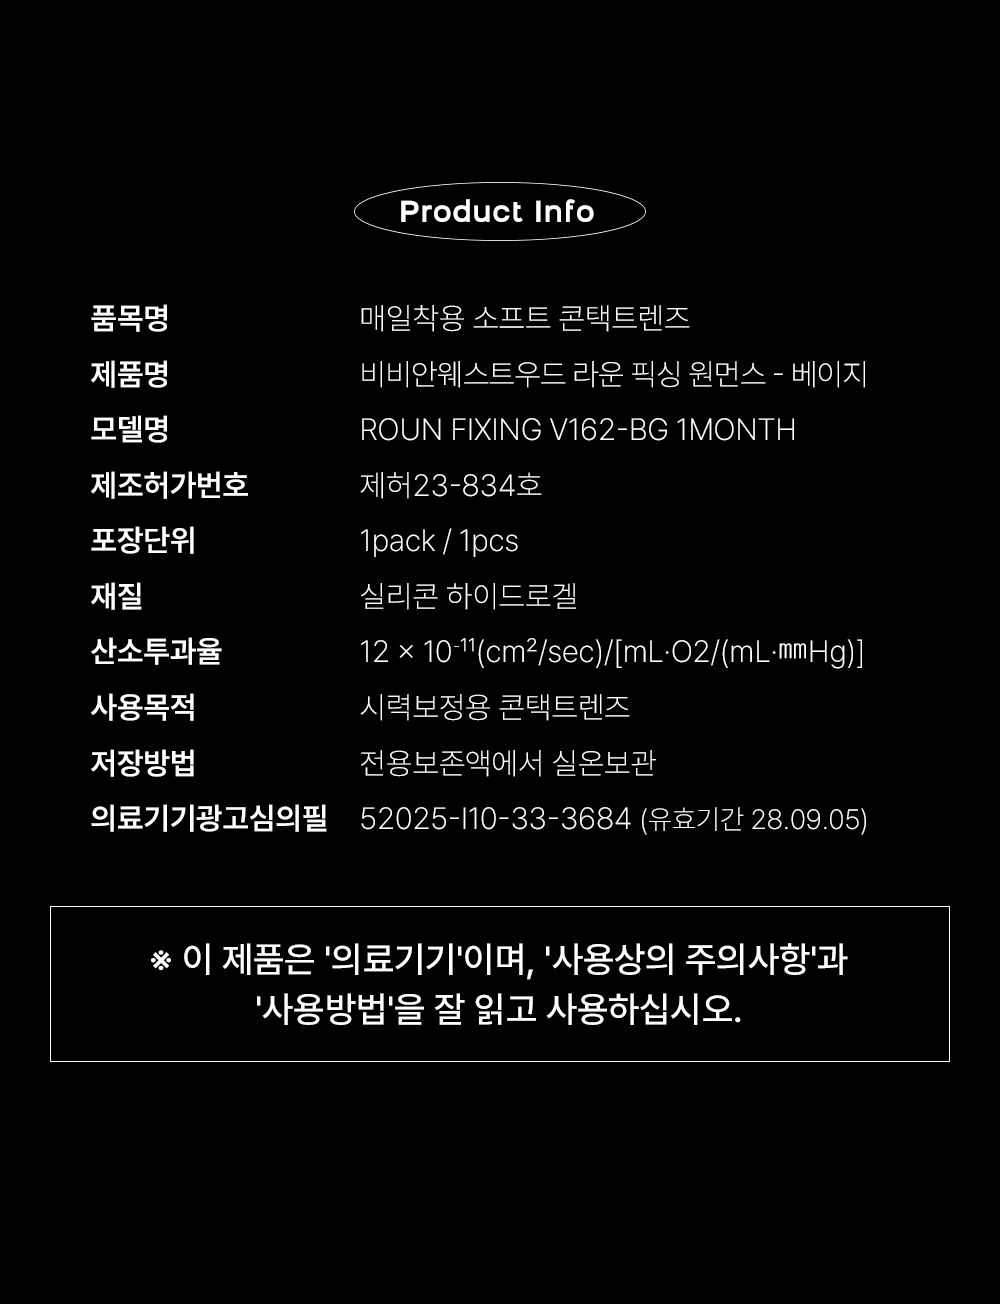

| 사용목적 | 시력보정용 콘택트렌즈 |

| 의료기기 제조 허가 번호 | 제허 23-834호 |

| 모델명 | ROUN FIXING V162-BG 1MONTH |

| 광고심의 필 (심의번호) | 52025-I10-33-3684 |